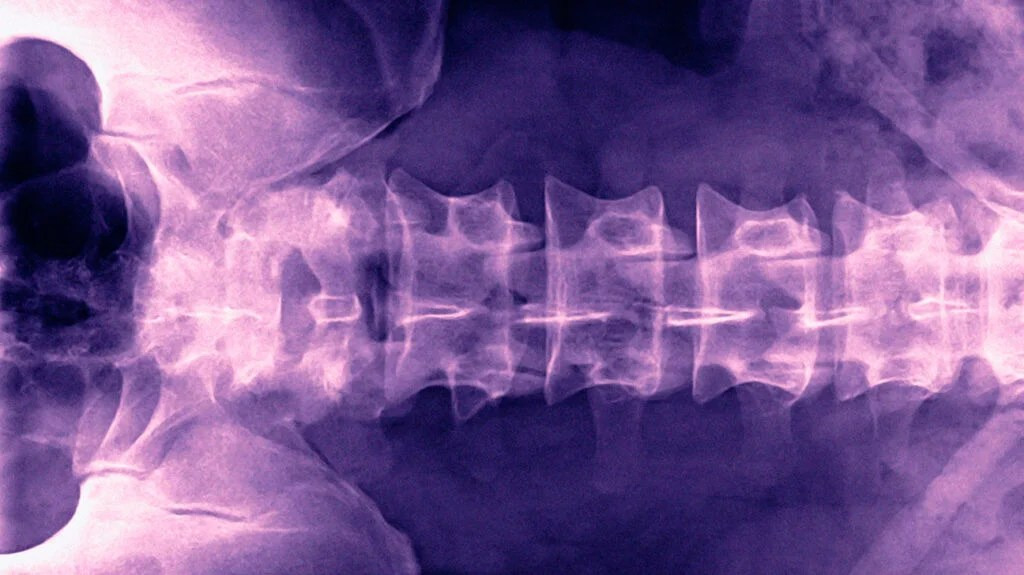

- 압박골절(압축골절)

외부 충격에 의해 뼈가 눌려서 납작하게 찌그러진 형태의 골절이다. 발가락보다는 주로 척추나 손가락 등에서 잘 발생하지만, 새끼발가락 끝부분이 강한 압력을 받을 경우 생길 수도 있다. 비교적 복잡한 골절로 간주되며, 뼈의 회복에 시간이 걸린다. - 폐쇄성골절